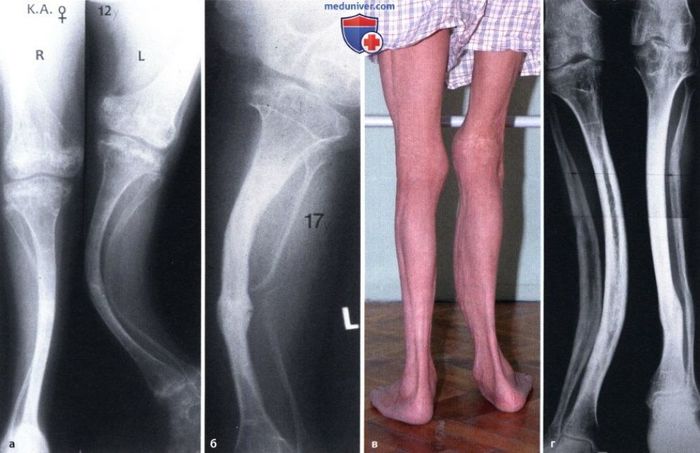

IV тип похож на первый но протекает в более тяжелой форме. В конечном итоге общий признак для всех типов одинаков: кости очень легко ломаются и очень трудно срастаются и заживают. Следствием длительного заживления нередко становятся различные деформации, существенно затрудняющие передвижения. У детей с ранней формой заболевания отмечаются несовместимые с жизнью внутричерепные родовые травмы, синдром дыхательных расстройств, респираторные инфекции. Поздняя форма несовершенного остеогенеза характеризуется типичной триадой симптомов: повышенной ломкостью костей, главным образом, нижних конечностей, синевой склер и прогрессирующей тугоухостью.

Применяются и хирургические ортопедические методы, например, остеосинтез при помощи телескопических штифтов, вводимых вовнутрь кости в детстве и «растущих» вместе с ней. Физиотерапия, которая сводится к улучшению мышечного каркаса, а также совершенствованию координации, что позволяет избегать падений, а значит и переломов. Хороший эффект показывает гидротерапия, особенно для ускорения заживления уже существующих переломов. Пациенты принимают витамин Д3 и препараты кальция.

С хирургической стороны давно назрела идея, что для механического укрепления "хрустальных" костей нужно вставлять в них металлические стержни. Проблем было несколько. Первая - оперировать нужно до того, как ребёнок вырастет, а следовательно, имплантируемая конструкция (словосочетание-то какое красивое!) должна "расти" вместе с дитём. Ну, тут решение простое. Всем известны телескопические конструкции на манер раздвижной антенны приёмника. Проблема вторая состоит в том, что для восстановления правильной ориентации ноги или руки во время установки конструкции в кость, ранее сломанную далеко не один раз, приходится снова ломать, часто в нескольких местах, и собирать в правильном положении, буквально нанизывая по частям на металлический стержень. Сравнение, произнесённое дружбаном, я не стану здесь приводить, сами знаете, какие у медиков шуточки бывают циничные! Так вот, на этом этапе возникает другая проблема: части костей не должны вращаться после операции, т.е. должны быть "ротационно стабильными". И вот эта-то проблема и была решена харьковскими врачами. Решение оказалось вполне простым и на сегодняшний день по этой методике пролечен уже не один десяток пациентов. Понятное дело, что всех тонкостей лечения я не расскажу в силу отсутствия профильного образования, а фотками своих пациентов друг не поделится по этическим соображениям.